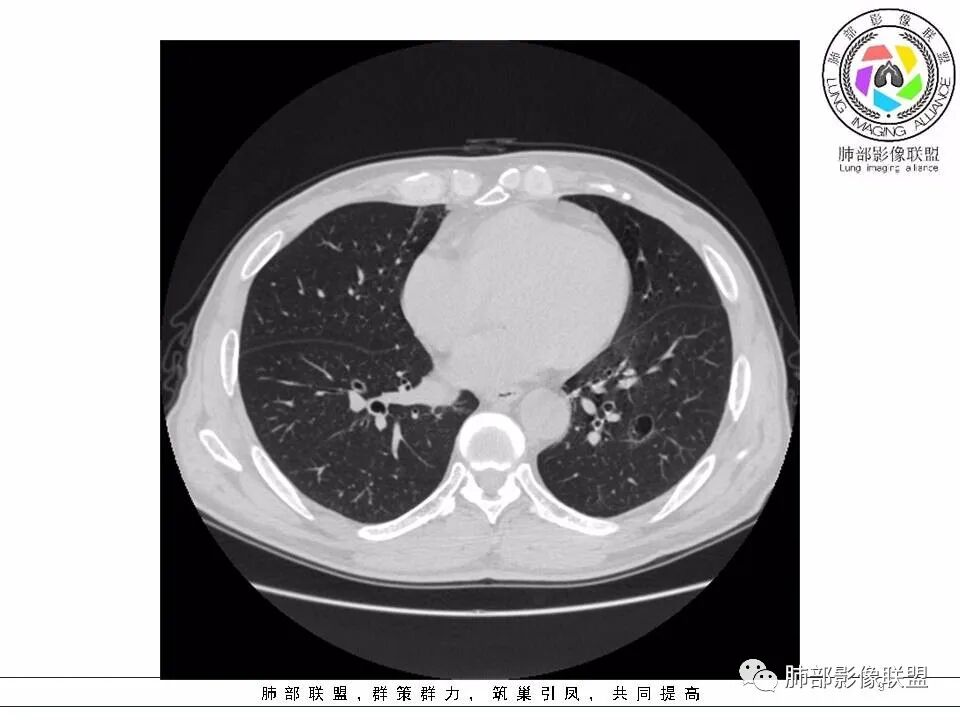

2.左肺下叶外基底段囊腔样病灶,轮廓柔和,壁厚薄不均,见壁结节。内见分隔或脊状突起。腔内见血管穿行。

这是有“故事”的囊!

3.囊壁外环以磨玻璃影,边界较清楚。

1.囊腔壁厚薄不均,壁结节,内有分隔,其内有血管穿行,指向新生物。

2.临近有边界清楚磨玻璃影,指向腺癌。